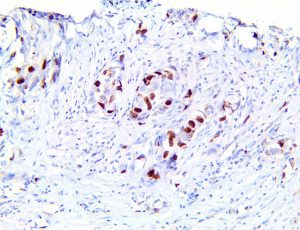

It is the ICU physician who is most likely to witness one of the deadliest manifestations of the abnormal immunological response, the cytokine storm syndrome (CSS). This response is also referred to by some as the cytokine release syndrome (CRS). CSS is characterized by continuous activation and expansion of macrophage and lymphocyte populations, which secrete large amounts of cytokines, causing the cytokine storm. This massive cytokine release is akin to hemophagocytic lymphohistiocytosis (HLH) disease, a syndrome characterized by initial unchecked and persistent activation of cytotoxic T lymphocytes and NK cells.

Clinical and laboratory manifestations of HLH include fever, enlarged liver and/or spleen, neurologic dysfunction, coagulopathy, liver dysfunction, cytopenias (i.e., low levels of erythrocytes, leukocytes, and/or platelets), hypertriglyceridemia, hyperferritinemia, hemophagocytosis, and eventually diminished NK cell activity as the immune system becomes progressively paralyzed. HLH can be familial (primary HLH) or secondary to another disease process (sHLH), such as rheumatic disease, in which it is referred to as macrophage activation syndrome (MAS, characterized by elevated ferritin).